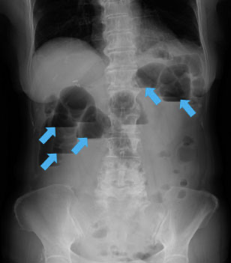

经问诊,如怀疑肠梗阻,则进行血液检查,确认有无脱水情况,同时进行腹部X光检查。通过X光检查确认有无肠管扩张及气液平面(肠管内积气与积液导致其分界线在X光片中形成鲜明的水平镜面)等肠梗阻特征。

腹部X光影像(气液平面多发,可见镜面(蓝色箭头所示)):